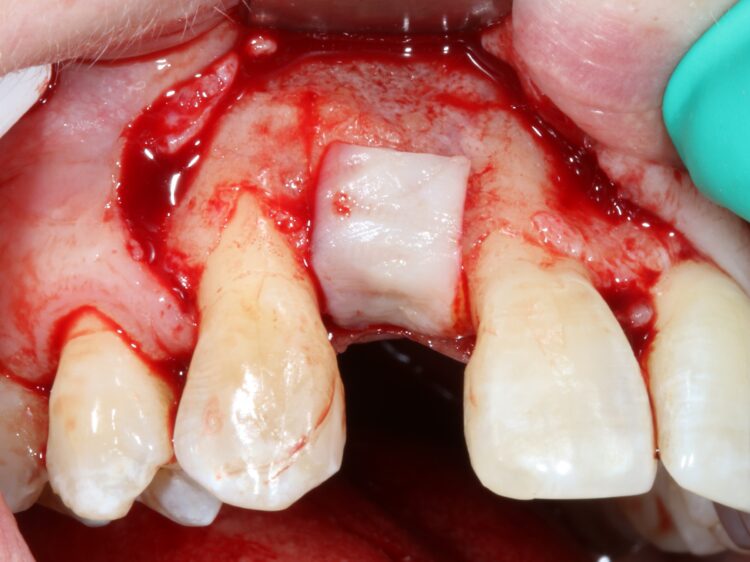

Implant placement and soft tissue grafting

The second surgery involved a palatal crestal incision and a full thickness flap elevation revealing good turnover of bone graft into host bone. A bone level implant was placed in an appropriate three-dimensional position completely surrounded by new bone and no additional bone grafting was required. A 4mm healing cap was placed.

A free gingival graft was taken from the palate below the upper right molar teeth and the epithelium was removed on the surgical table. The connective tissue strip of graft was then placed on top of the healing cap (and suspended over the healing cap) and secured to the palatal flap with 6.0 PGA Resorba Sutures. Finally, the buccal flap was closed with complete primary intention wound healing using 6.0 Prolene.